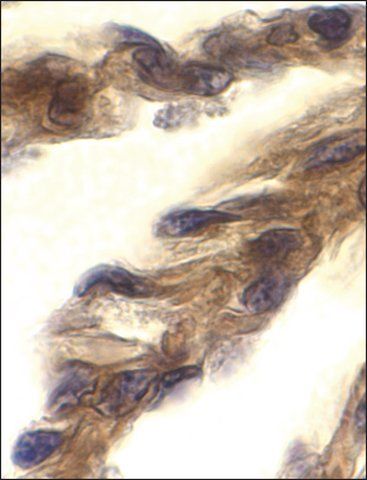

| technique(s) | immunohistochemistry: 1:10-1:50 western blot: 1:1000 |